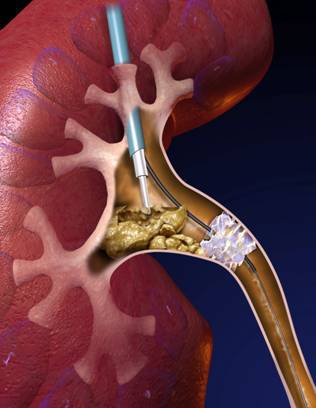

经皮肾镜碎石取石术(PCNL):是指通过腰部皮肤到肾脏之间制作一微小通道,通过此通道将纤细的内窥镜伸入到肾脏的结石部位,利用腔内碎石、取石器械,将结石击碎、取出的微创技术。也就是首先在患者腰背部打一个约筷子粗细的洞,建立一个隧道并看到“可恶”的石头之后,再利用我们的内窥镜以及碎石设备(比如传说中高大上的激光、超声、气压弹道等),像武侠小说中的六脉神剑一般,很快地结石粉碎掉,然后将结石从该隧道冲洗出体外,最后放置肾造瘘管以及输尿管支架管引流,完成整个手术过程。

相较于传统手术刀口要像蜈蚣一般长达20厘米,且依靠医生手指伸进病人肾脏内掏石头,针对复杂结石,在肾脏内分支很多,开刀手术要想取干净这些多分支的结石是很难的,就算取了大部分结石,也是将肾脏剖开,取出结石后,再将肾脏钉合缝合起来,牺牲了大量的肾脏正常组织功能,结石虽然取出来了,肾功能也丢失了不少,容易造成“同归于尽”的结局,很多病人早年经历开放肾切开取石后出现肾萎缩的结果。而经皮肾镜刀口只有普通筷子直径那么大,所以该技术具有创伤面小,恢复快的优点。而且通过内窥镜的探查,可以发现的结石的各个分支,我们可以很直观的看到结石并粉碎,而不是靠飘忽的经验、手感去掏,所以取干净结石的几率也是大大增高,同时最大限度的保留了肾功能,因而随着这一技术的诞生和发展成熟,目前已经取代传统的开刀手术成为了复杂肾结石治疗的“金标准”。

3、碎石取石

直捣肾脏之后,置入内窥镜,利用持续的水流的冲开最后一道防线,杀向我们的敌人——结石。神兵天降,让*弹子**飞一会儿吧!结石到了最危险的时候!这时我们的终极*器武**,气压弹道、钬激光或者超声这三大秘密*器武**就粉墨登场了!“气压弹道”就好比机关机枪,突突突突将结石打个片甲不留,如降龙十八掌般气势如虹;“钬激光”就像把镭射枪,如同六脉神剑般悄然间把结石消融掉;而“超声碎石”则是把超声波枪,不知不觉让结石粉身碎骨并直接吸出肾脏外,好比化骨绵掌。碎石过程中,整个手术室就像维也纳金色大厅,响起了一首首欢快的碎石乐章!